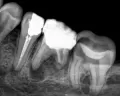

У меня обнаружили 2 кисты на 36 зубе. На одном корне киста маленькая, на втором большая. Снимок прилагается. Врач-терапевт сначала сказал, что нужно удалить кисту, а потом сказал лечить. Просверлил зуб, оставил открытым, сказал полоскать солевым раствором и принимать Кетарол.